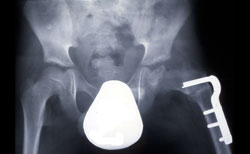

The most common surgical procedure for treating Perthes disease is an osteotomy. In this type of procedure, the bone is cut and repositioned to keep the femoral head snug within the acetabulum. This alignment is kept in place with screws and plates, which will be removed after the healed stage of the disease.

In many cases, the femur bone is cut to realign the joint. Sometimes, the socket must also be made deeper because the head of the femur has actually enlarged during the healing process and no longer fits snugly within it. After either procedure, the child is usually placed in a cast for 6 to 8 weeks to protect the alignment.

An osteotomy of the femur places the femoral head in a better position to heal.

Courtesy of Texas Scottish Rite Hospital for Children